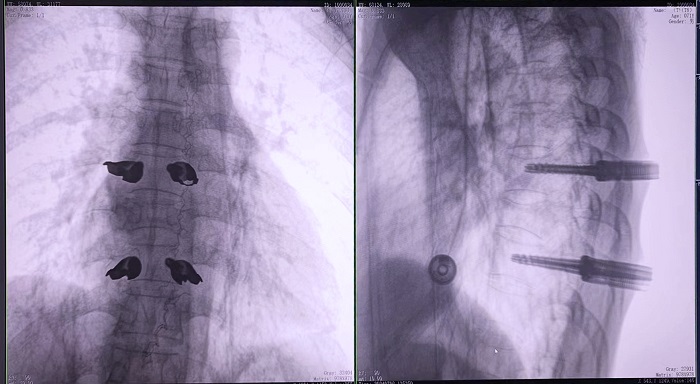

③機器人輔助胸椎手術操作難點之精準置釘

傳統開放手術中,胸椎的手術視野相對受限,螺釘的置入主要依賴于醫生的經驗和手感,存在一定的主觀性。

普愛醫療手術導航定位系統解決方案

普愛醫療骨科手術機器人的高精度機械臂,按照規劃好的路徑及角度,自動精準定位穿刺點,醫生打入克氏針后,正側位圖像顯示精度滿足預期,醫生完成置釘等后續手術操作。

機器人做胸椎置釘手術